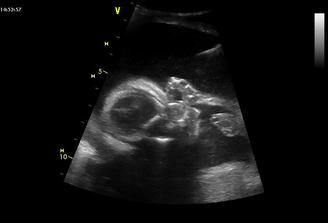

11.11. Gennet - NT screening - nedopadl úplně dobře, sice screening negativní ale Ductus Venosus abnormální, což dle paní doktorky

nemusí znamenat nic, nebo vývojovou vadu srdce. Takže musíme počkat do 16 týdne, kdy by se mělo poznat víc. 15.12. jdeme ke genetikovi, tak doufám, že bude vše ok.

11.1. - velký UTZ v Gennetu - mimi má vše co má mít. Srdíčko je také v pořádku. Málem nám paní doktorka prozradila pohlaví, ale včas jsme zasáhli, i když tatínek byl na vážkách. Mimi má 395 g.